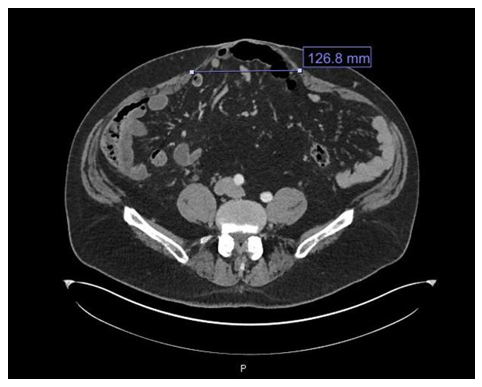

A preoperative CT-scan of the abdomen and pelvis showcased a midline ventral hernia at the level of the umbilicus and width of the hernia at its widest part was 12 cm. The external oblique, internal oblique, and transversus muscles were relaxed and not in a taut position (Figure 2). A preoperative nasal swab tested positive for methicillin-resistant Staph aureus, and the patient was given a decolonization with mupirocin ointment to the external nares twice a day for seven days and a Hibiclens shower daily for 7 days before surgery.

Figure 2 Preoperative CT scan at a level just below the umbilicus showing a broad-based ventral hernia containing nondilated loops of small bowel and colon. The distance between the edges of the rectus muscle was approximately 12 cm in length.